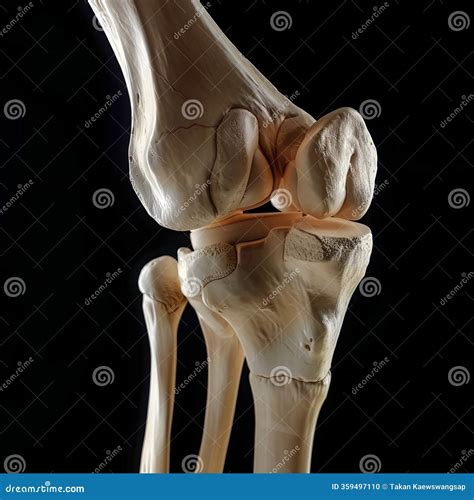

Detailed view of human knee anatomy

The cartilage found in the knee is primarily articular cartilage, a type of hyaline cartilage that covers the ends of the bones. Unlike other tissues in the body, it has a unique composition that allows it to withstand significant compressive forces. It consists of a dense network of collagen fibers and proteoglycans, which attract water to create a gel-like consistency.

Because knee joint cartilage is avascular—meaning it lacks a direct blood supply—it relies on synovial fluid to obtain nutrients and remove waste products. This process, known as imbibition, occurs during the compression and release cycles of movement, which is why consistent, low-impact exercise is essential for its health.